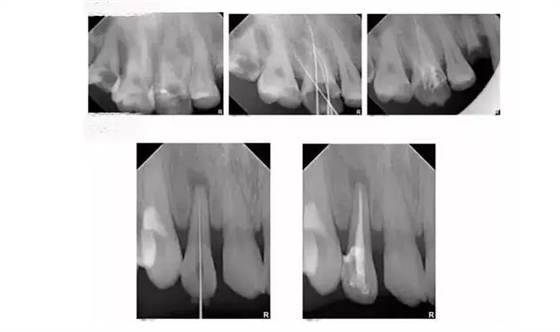

根管治療時,拍牙片是必要的,并且至少要保證3張牙片。

第一張:在治療前,幫助醫(yī)生了解牙根的基本情況,如根管預備是否到位等,并制定計劃。

第二張:在治療中,幫助醫(yī)生了解治療情況,如根管預備是否到位等,并指定下一步的計劃。

第三張:在治療結束后,幫助判定根管填充質量,發(fā)現(xiàn)問題及時補救。